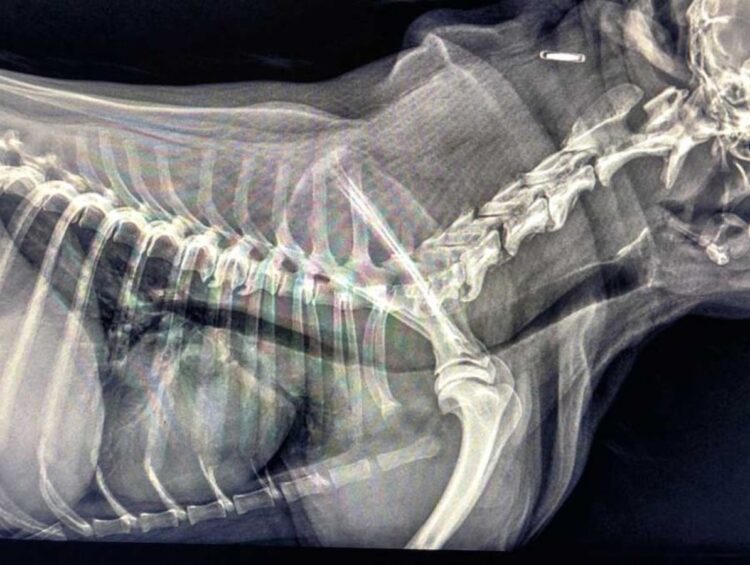

Źródło: https://wetgliwice.pl/ Zapadanie tchawicy u psów (TCS-Tracheal Collapse Syndrome) Zapadanie tchawicy u psów (TCS-Tracheal Collapse Syndrome) jest przewlekłą chorobą układu oddechowego obserwowaną głównie u raz małych …